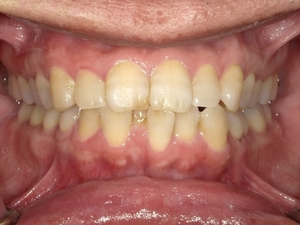

○ご相談内容:下の歯のがたつき○矯正の種類:マウスピース型矯正「クリアコレクト」○治療期間:10週間○治療費用:66万円(税込)